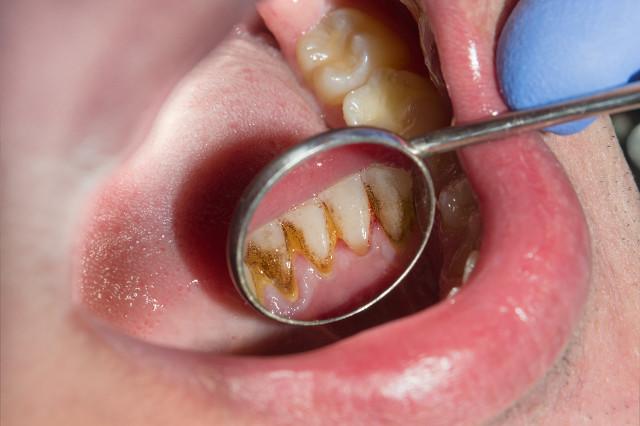

Kurz über die Entstehung von Zahnstein: zunächst wird die Oberfläche der Zähne bilden einen dünnen Film, und dann die Bakterien werden eine nach der anderen adsorbiert werden, gepaart mit Speiseresten, Kalziumsalze, etc. allmählich mineralisiert und fest an der Oberfläche der Zähne, zu diesem Zeitpunkt, egal wie viel Bürsten kann nicht gereinigt werden.

Diese klebrigen Filme haften an den Zähnen und wenn sie nicht rechtzeitig entfernt werden, beginnen sie innerhalb von 14 Tagen oder weniger zu verkalken und bilden allmählich Zahnstein.

Wenn sich der Zahnstein gerade erst gebildet hat, ist die Textur noch relativ weich, so dass die Chancen gut stehen, dass er sich von selbst entfernen lässt; ist dies der Fall, wird er im Laufe der Zeit langsam immer härter und haftet fest an der Zahnoberfläche.

Eine harte, solide, alte Rechnung dauert in der Regel Monate oder sogar Jahre.